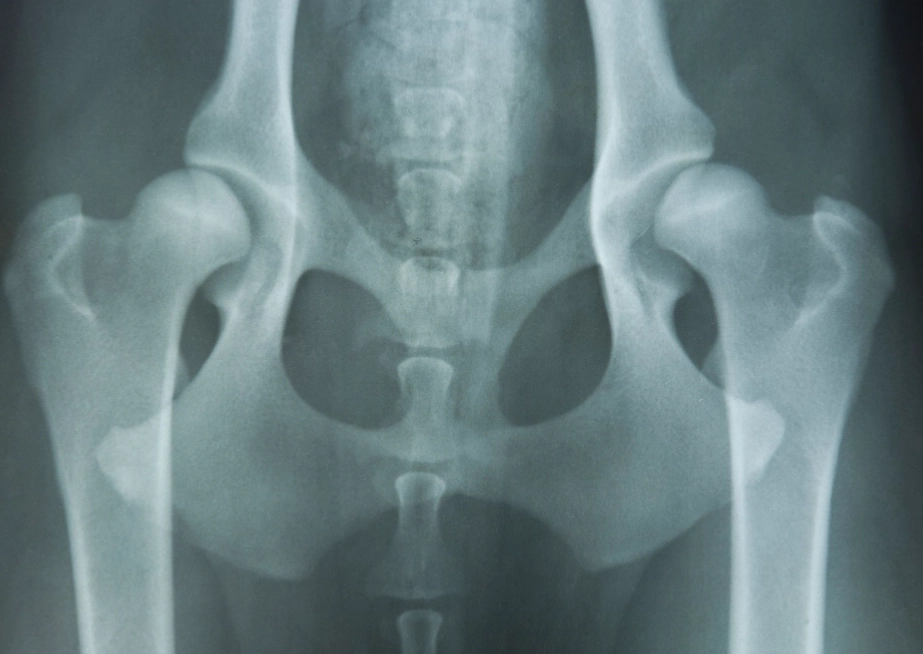

Let's break it down simply. A healthy hip is a ball-and-socket joint that fits together snugly. With hip dysplasia, the socket is too shallow, and the ball (the head of the femur) is loose. This poor fit causes abnormal wear and tear every time the dog moves. It's not just arthritis—arthritis is the result of the instability. The condition is primarily genetic, but factors like rapid growth, improper nutrition, and excessive exercise in puppyhood can worsen it.

- X-Rays (Radiographs): This is the gold standard. But not all X-rays are equal. A quick, awake X-ray often misses the true degree of laxity. For a definitive diagnosis, especially in young dogs, a hip-extended ventrodorsal view and often a PennHIP or Dorsal Acetabular Rim (DAR) view are needed. PennHIP, in particular, can detect laxity in puppies as young as 16 weeks, which is a game-changer for early intervention.